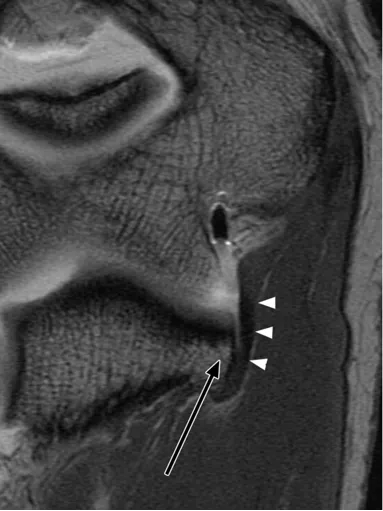

后方滑膜皱襞,是肘关节内滑膜折叠形成的结构,若受到反复刺激可能诱发炎症反应。

(a)26 岁男性受试者的横轴位质子密度加权脂肪抑制磁共振成像,以及(b)对应的示意图,均显示出后方滑膜皱襞(箭头所示)。图中 AM 代表肘肌。